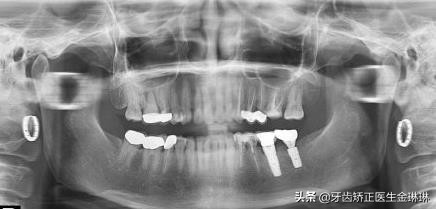

真牙和种植牙示意图

种植牙复诊一般都需要拍片的,主要是因为种植牙的人工牙根是植入到牙槽骨里面的,肉眼无法的查看人工牙根在里面的情况,只能通过牙片把人工牙根和牙槽骨的情况展现出来,查看种植体是否有松动或者炎症等情况。